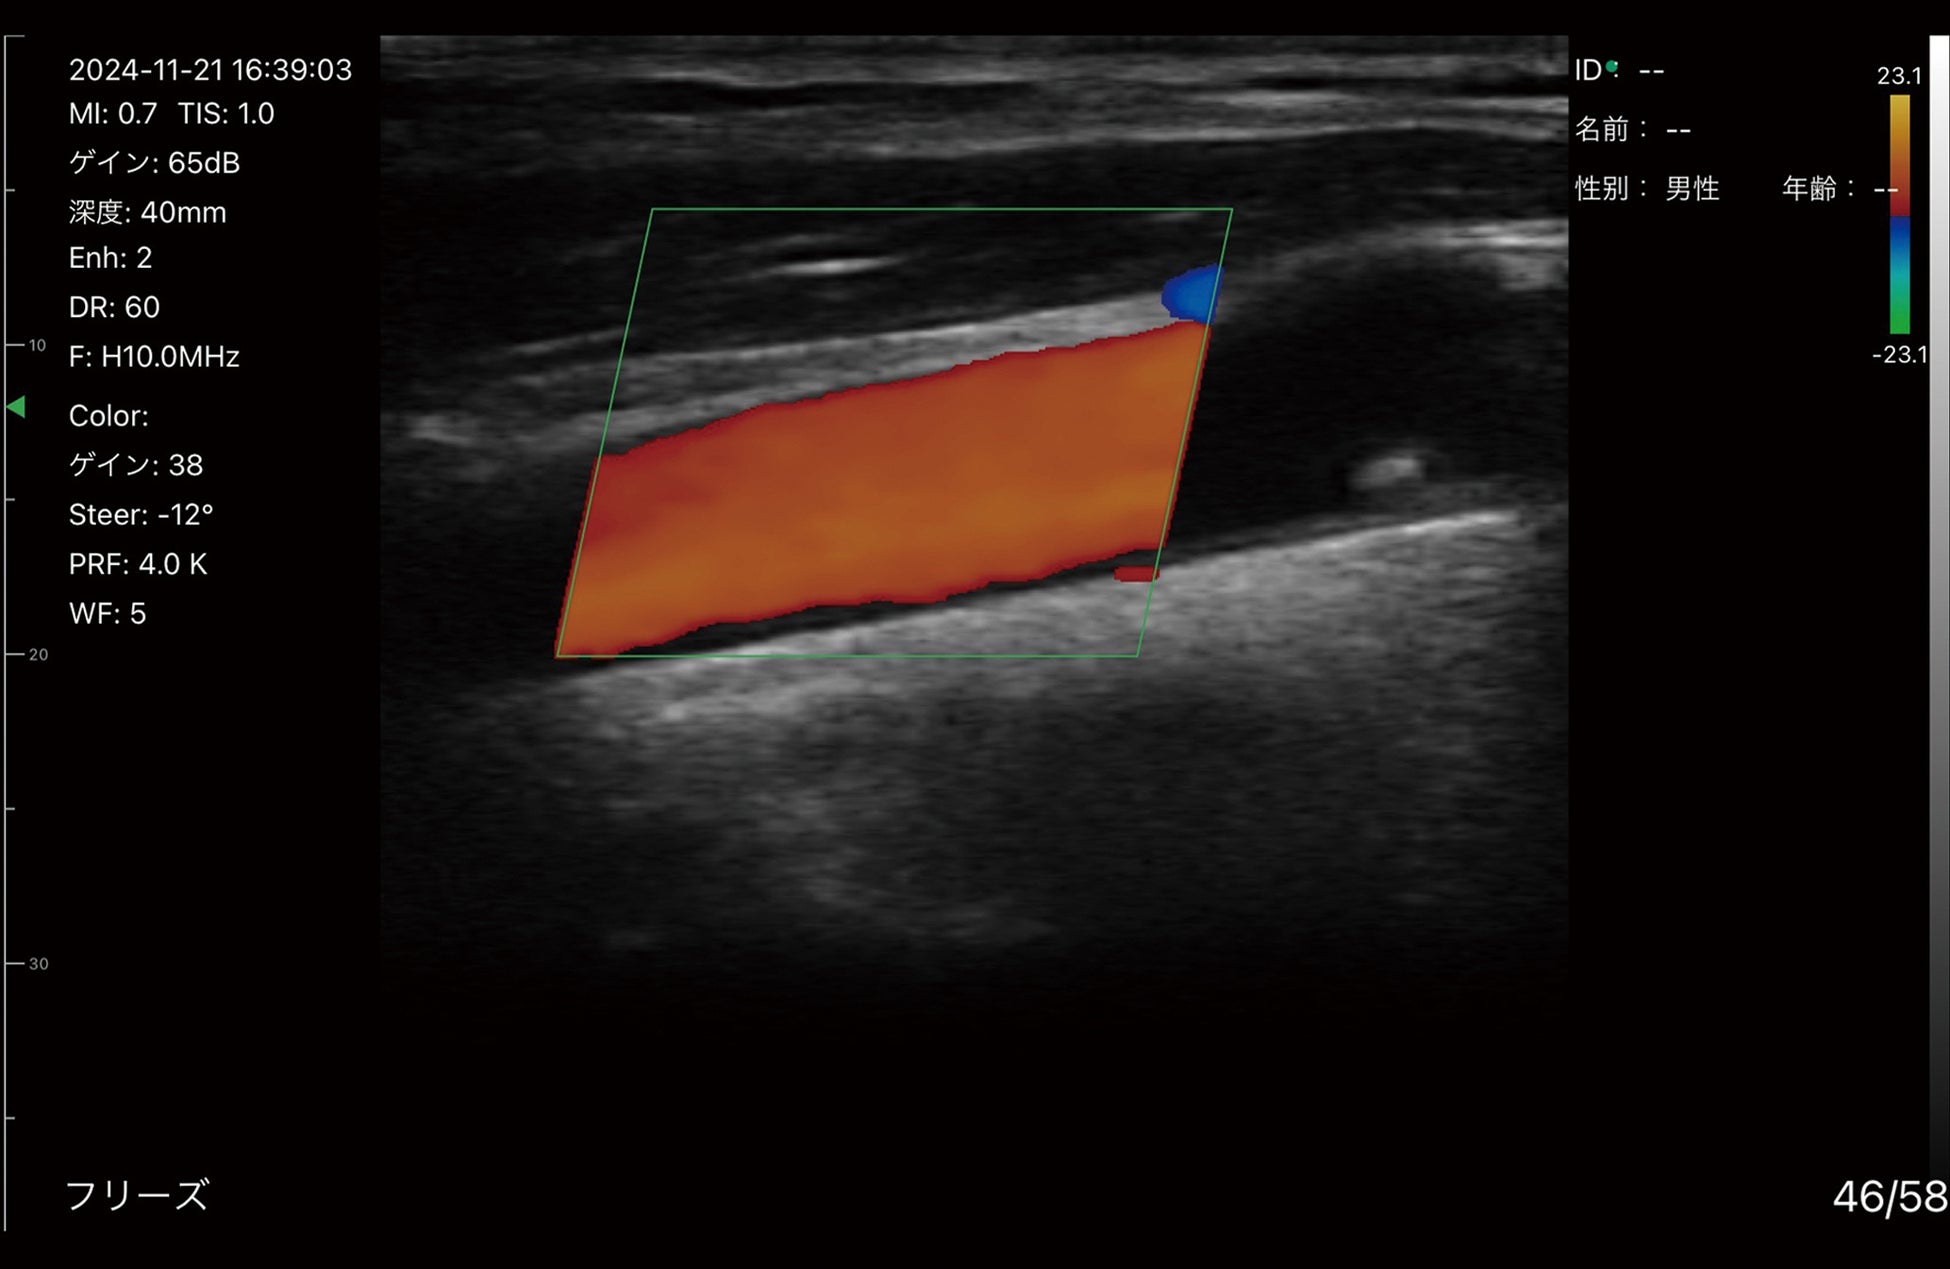

コンベックスとリニアプローブを一体化したデュアルプローブと、血流を視覚的に表示するドプラ機能の搭載により、1台で幅広い領域/部位へ使用可能。

・カラー・パワードプラー